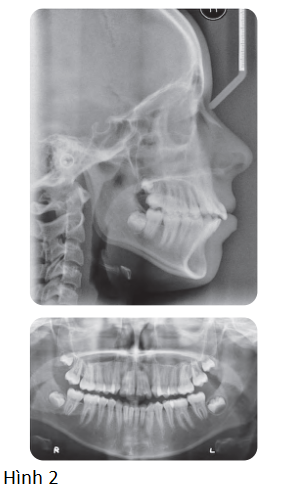

Bệnh nhân nữ 16 tuổi có sai khớp cắn hạng III trên nền xương hạng II nhẹ với tăng kích thước dọc phức tạp bởi chen chúc nhẹ và hô 2 hàm (Hình 1, Hình 2)